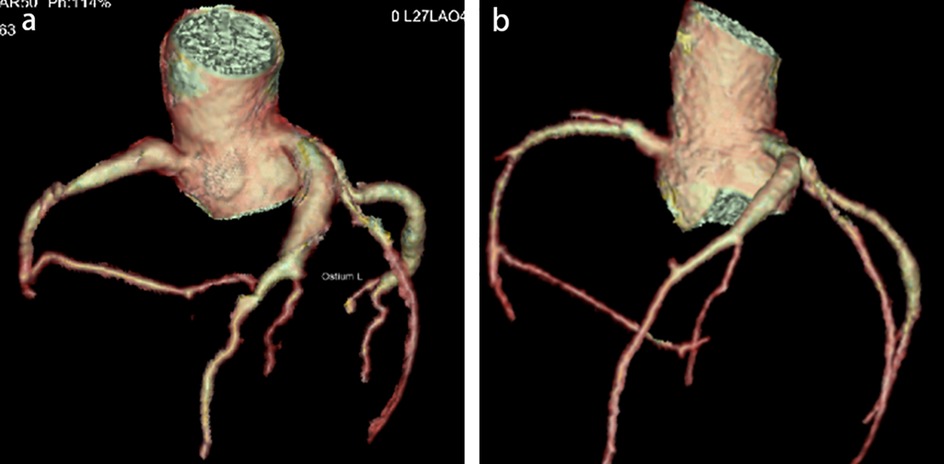

Physical examination upon admission: Temperature 38.4°C, no obvious conjunctival congestion, no dryness or redness of the lips, no “strawberry tongue,” no changes in extremities, several enlarged lymph nodes palpable in the neck. Scattered red rashes were observed over the whole body, raised above the skin surface, non-blanching on pressure, partially confluent, and without significant pruritus. Dry and moist rales were heard in both lungs. Abdomen slightly distended, with tenderness in the upper abdomen but no rebound tenderness. The liver is approximately 2 cm below the costal margin, and the spleen is approximately 1.5 cm below the costal margin. Blood pressure is significantly reduced (71/45 mmHg). Laboratory examinations: WBC count normal (4.79 × 109/L), CRP elevated (158.14 mg/L), erythrocyte sedimentation rate (ESR) slightly elevated (21 mm/h), PLT count reduced (44.00 × 109/L), Hb reduced (104 g/ L), SAA elevated (321.48 mg/L), IL-6 elevated (143 pg/mL), D-dimer elevated (7.23 µg/mL), albumin reduced (26.00 g/ L), transaminases elevated (ALT 136 U/L, AST 120 U/L), and pro-brain natriuretic peptide (pro-BNP) elevated (6,968 pg/mL). Chest computed tomography (CT) suggested pneumonia with pleural effusion (Figure 1), and chest ultrasound showed left-sided pleural effusion of 51 mm. Abdominal CT revealed peritoneal effusion with cholecystitis, and ultrasound showed a thickened gallbladder wall and splenomegaly. Based on the child's clinical symptoms and auxiliary examination results, the preliminary diagnosis was severe pneumonia complicated by septic shock. Methylprednisolone was administered for anti-inflammatory treatment, meropenem for infection, low molecular weight heparin for anticoagulation, fluid resuscitation, dopamine and dobutamine for blood pressure support [although foreign literature had already reported that adrenaline and noradrenaline were the firstline inotropic agents for septic shock, the guidelines in China were not updated until 2025 (5)], albumin administration for hypoalbuminemia, and intravenous immunoglobulin (IVIG, 1 g/kg/day for 2 days) for immunomodulation. After 5 days of treatment (on day 12 of illness), the child still presented with recurring fever and abdominal pain, but the rash had gradually subsided. Physical examination revealed slight conjunctival congestion, slightly red lips, and a strawberry tongue. Several enlarged lymph nodes were palpable in the neck. Blood tests indicated elevated serum ferritin levels (2,086 ng/mL) with nagetive blood culture report, so KD was highly suspected, and further tests were conducted. Neck ultrasound showed enlarged cervical lymph nodes (2 cm × 2 cm), and cardiac echocardiogram revealed left main coronary artery (LMCA) dilation (4.0 mm, Z score + 2.93), left circumflex artery dilation (LCX 3.2 mm, Z score + 3.15), left anterior descending artery dilation (LAD 4.4 mm, Z score + 5.73), and right coronary artery widening (RCA 3.5 mm, Z score + 2.36), with mild pericardial effusion (Figure 2). Hemophagocytic cells were shown on the bone marrow biopsy (Figure 3). Considering the progressive increase in ferritin levels, a sharp decrease in platelets, elevated AST, and reduced fibrinogen (from 3.52 to 1.39 g/L) during the course of illness, the child was diagnosed with KDSS, MAS, severe pneumonia, and cholecystitis. On the 12th day of illness, IVIG (2 g/kg) was administered along with a methylprednisolone pulse therapy (30 mg/kg/day for 3 days) and oral aspirin 100 mg daily for antiplatelet therapy due to his poor liver function. After finishing IVIG infusion (on day 13 of illness), the child's temperature normalized, follow-up chest CT indicated improvement of pneumonia, and corticosteroids were tapered. However, on day 20, fever recurred when methylprednisolone was tapered to 1 mg/kg/day, accompanied by mild erythema on both palms. CRP reelevated to 38.43 mg/L, suggesting an IVIG non-responding KD. Echocardiography showed a progressive CAA (Table 1). So infliximab (5 mg/kg) combined with methylprednisolone (2 mg/kg/day) was given. His fever and symptoms resolved completely, and the corticosteroid was tapered within 3 weeks. Prior to discharge (on day 33 of illness), an echocardiogram showed multiple CAAs (LMCA 3.7 mm, Z score + 2.24; LCX 4.3 mm, Z score + 4.9; left ascending artery (LAD) 6.3 mm, Z score + 10.49; RCA 4.3 mm, Z score + 4.14) (Figure 2). PLT count increased to 408 × 109/L, and then oral rivaroxaban 7.5 mg and aspirin 100 mg daily were prescribed for antithrombosis (6), and coronary artery computed tomography angiography (CTA) was performed (Figure 4). The child was discharged after 30 days of hospitalization and was scheduled for regular outpatient follow-up. The CTA 3 months after discharge showed significant improvement in all three branches, with the maximum diameter 6.8 mm in LAD (Figure 4); therefore, rivaroxaban was replaced with clopidogrel. At the last follow-up (6 months after the onset of illness), the echocardiogram showed significant regression of the coronary aneurysms (LMCA 3.2 mm, Z score +1.08; LCX 2.6 mm, Z score + 1.17; LAD 5.0 mm, Z score + 7.24; RCA 2.7 mm, Z score + 0.58), and only aspirin was continued.

Figure 4. Coronary artery computed tomography angiography (CTA, 3 months after the onset of illness). CTA before discharge (a) shows long segment aneurysms in RCA, LAD, and LCX, respectively, with a maximum diameter of 6.8 mm in LAD. CTA at 3 months follow-up (b) shows significant improvement in every three branches, with a maximum diameter of 4.8 mm in LAD.